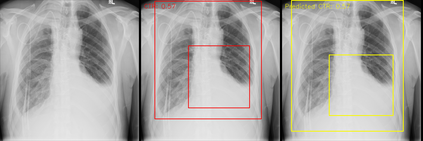

We propose an automated method based on deep learning to compute the cardiothoracic ratio and detect the presence of cardiomegaly from chest radiographs. We develop two separate models to demarcate the heart and chest regions in an X-ray image using bounding boxes and use their outputs to calculate the cardiothoracic ratio. We obtain a sensitivity of 0.96 at a specificity of 0.81 with a mean absolute error of 0.0209 on a held-out test dataset and a sensitivity of 0.84 at a specificity of 0.97 with a mean absolute error of 0.018 on an independent dataset from a different hospital. We also compare three different segmentation model architectures for the proposed method and observe that Attention U-Net yields better results than SE-Resnext U-Net and EfficientNet U-Net. By providing a numeric measurement of the cardiothoracic ratio, we hope to mitigate human subjectivity arising out of visual assessment in the detection of cardiomegaly.